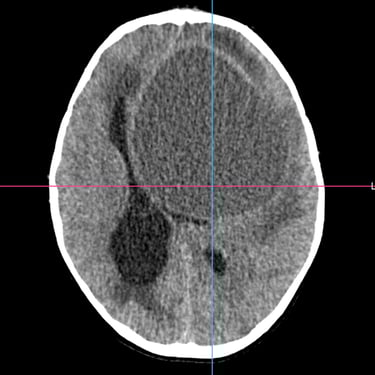

El absceso cerebral es una infección localizada del parénquima cerebral que produce acumulación de pus e inflamación, generando cefalea, fiebre, alteración del estado de conciencia o déficit neurológico focal. El diagnóstico temprano es fundamental para evitar complicaciones graves. La tomografía cerebral con contraste es el estudio de elección inicial, ya que permite visualizar una lesión hipodensa con realce en anillo característico. Posteriormente, la resonancia magnética complementa la evaluación. El tratamiento combina antibioticoterapia dirigida y, en casos seleccionados, drenaje quirúrgico o resección. La detección oportuna mediante imágenes mejora significativamente el pronóstico del paciente.